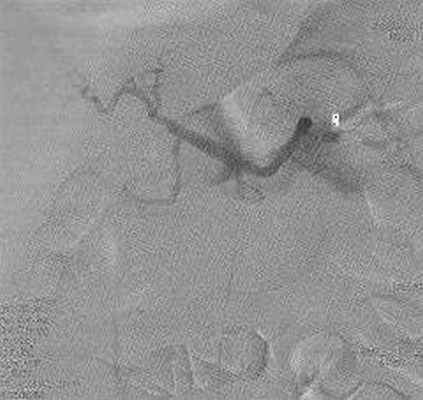

Больной Е., 61 год, поступал в ГКБ № 57 г. Москвы в плановом порядке 15.05.2014. При поступлении жалоб не предъявлял. Из анамнеза страдает язвенной болезнью желудка 8 лет. В 2013 г. выявлена аденокарцинома тела желудка, T4N0M0, выполнена лапароскопическая гастрэктомия, холецистэктомия, лимфоаденодиссекция D2 (январь 2014 г.). Послеоперационный период осложнился тромбозом левой ветви воротной вены, наружным желчным свищем, поддиафрагмальным абсцессом слева, который был дренирован. При обследовании по данным КТ-ангиографии выявлена аденома левого надпочечника и аневризма собственной печеночной артерии. Госпитализирован для дообследования и решения вопроса об оперативном лечении. При УЗИ лоцировать аневризму печеночной артерии четко не удалось. В плановом порядке выполнена селективная артериография, при которой выявлена аневризма общей печеночной артерии в средней порции, 10´20 мм (рис. 1). Диагноз подтвержден при КТ с контрастированием. Пациенту было решено выполнить оперативно лече-ние – эмболизацию псевдоаневризмы. 29.05.2014 г. левым трансаксилярным доступом установлен интродьюсер 6F. Селективно в стволе чревного ствола установлен гайд-катетер 6JR. Суперселективно проводник 0,014” проведен в полость аневризмы. Установлены две спирали Azur-18 (Terumo), 0,4´4 см и 0,8´14 см. Через 20 мин. выполнена контрольная ангиография − тромбоз основной полости аневризмы на 90% (рис. 2). Послеоперационный период протекал без осложнений. Жалобы пациент не предъявлял. Учитывая широкую шейку аневризмы и возможность миграции спиралей от дальнейшей эмболизации решено отказаться.

С целью контроля остаточной полости псевдоаневризмы пациенту через 8 дней была выполнена повторная артериография. Выявлено, что аневризма в области шейки не тромбирована, спирали Azur -18 располо-жены вне зоны контрастирования псевдоаневризмы (рис. 3). Подтекания контрастного вещества за пределы аневризмы и артерии не выявлено. Ангиографическая картина расценена, как миграция спиралей Azur -18 из контрастированного сегмента аневризмы в тромботические массы псевдоаневризмы периартериального пространства. Было решено выполнить имплантацию стент-графта. Из левого трансаксилярного доступа установлен интродьюсер 6F. Селективно в чревный ствол установлен гайд-катетер 6JR. Проводник Asashi 0,014’’ проведен в дистальную порцию ветви печеночной артерии. По проводнику без технических проблем проведен стент-графт 4,0 ´18,0 мм (Boston Sientiphic) и раскрыт в зоне шейки аневризмы под давлением 8 атмосфер. Контрольная артериография: аневризма не контрастируется, затеков контрастного вещества не отмечается (рис. 4). Послеоперационный период протекал без осложнений. Больной выписан на 3 сутки в удовлетворительном состоянии. Через 3 мес. пациент повторно был госпитализирован для выполнения контрольной артериографии. Жалобы пациент не предъявлял. Выявлено, что общая печеночная артерия не контрастируется в проксимальной трети (2 см) – тромбоз стент-графта. Однако дистальные отделы печеночной артерии заполняются по коллатеральным ветвям (рис. 5).